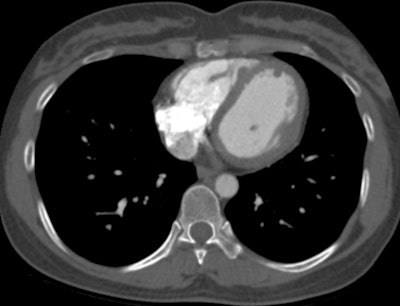

"Chest CT demonstrates poor sensitivity for detection of cardiac metastasis, with cardiac MRI performing much better. Still, neither CT nor MRI is as sensitive as [gallium-68 (Ga-68)] DOTATATE PET/CT for detection of neuroendocrine cardiac metastasis," noted Dr. John Renfrew and colleagues from the Mayo Clinic in Phoenix, Arizona, U.S.

Of the 26 cases, 17 also underwent a contemporaneous chest CT exam. Only one of these CT scans demonstrated evidence of neuroendocrine cardiac metastasis, Renfrew and colleagues reported.